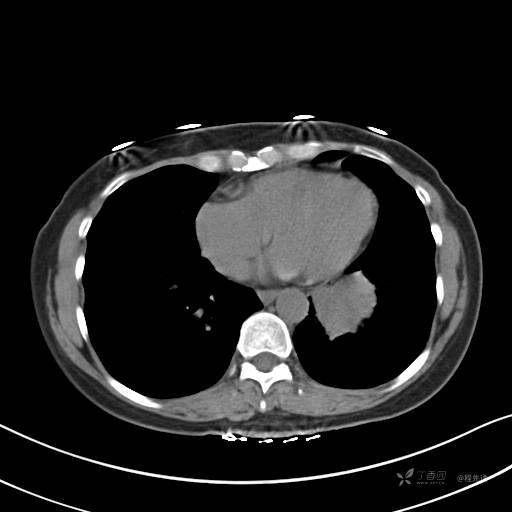

冠状位重建

CT值:平扫:31HU,动脉期:74HU,静脉期:84HU